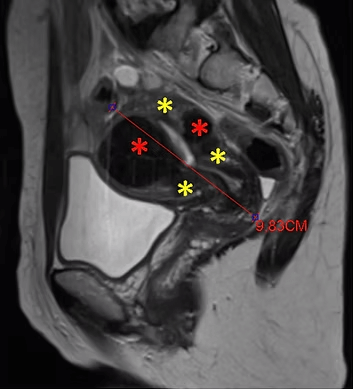

29 yaşında, adet uzaması, kansızlık ve sık idrara çıkma şikayetleri olan ve daha önce 2 kez miyomektomi olan hasta. Emar’da idrar kesesine bası yapan 85mm çaplı miyom (*) mevcut. Embolizasyondan sonra miyomun öldüğü ve küçüldüğü izleniyor. 7 ay sonra hasta şikayeti kalmamış ve 4 yıllık takip süresince yeni miyom oluşmamıştır.